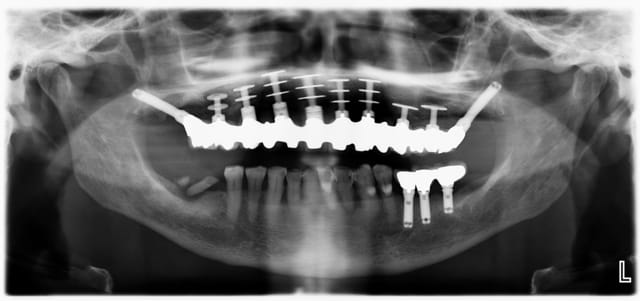

Au secours, mon implantologue est en vacances et j'aimerai donner un début de réponse à mon patient avant de partir en vacances.

On fait quoi avec les implants sup ?

Ben il est où le problème ?

Sur cette radio, on voit pas grand chose...

il y a des péri-implantites sur quasi tout les disk du haut, c'est cà?

Fabuleuses ces pano avec des diskimplants, ça defit notre mode de pensée implantaire actuel. En tout celui qui a traité ce patient n'était pas un manchot.

En pratique, c'est quoi le problème avec les disk ? On voit pas bien sur la pano periimplantite ? sinon il va y avoir besoin d'encore un peu de titane en secteur 4

Non, ce n'est pas un problème de tourne disque mais plutôt de peri-implantite dans le secteur antérieur.

Effectivement, pas de mobilité.